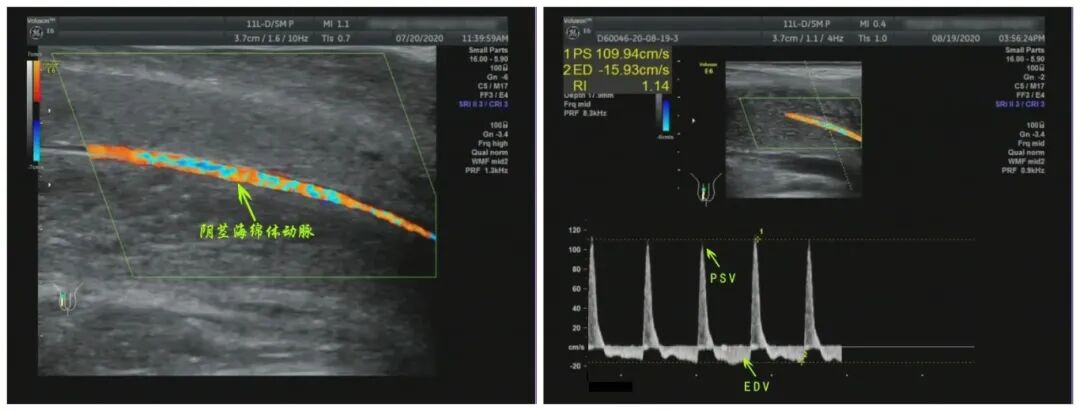

血管功能问题也有可能导致勃起功能障碍,阴茎血流超声检查(CDDU)是目前诊断血管性勃起功能障碍的金标准

通过超声可以直接观察阴茎血管的病变情况(纤维斑块、血管钙化等),测定阴茎血流速度,评价阴茎的血管功能,为血管性ED的诊断提供依据。

用彩色多普勒超声检查与阴茎海绵体内血管活性药物注射结合的方法可以有效鉴别血管性或非血管性ED、动脉性或静脉性ED。